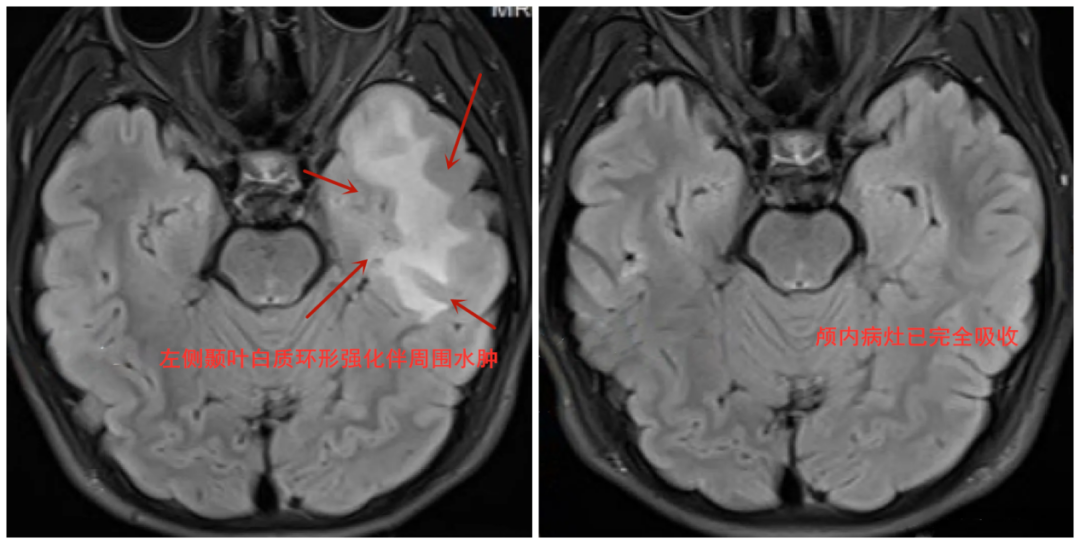

14歲的男孩俊俊在睡眠中 突發(fā)四肢抽搐、神志不清 家人緊急將他送往醫(yī)院 根據(jù)檢驗結(jié)果,醫(yī)生高度懷疑俊俊可能是寄生蟲感染侵及顱腦,導致腦部異常放電引起癲癇發(fā)作。經(jīng)完善病原學檢查,俊俊確診為弓形蟲感染引發(fā)顱內(nèi)病變。 那么,俊俊究竟是怎樣感染弓形蟲的? 原來,俊俊家四年前養(yǎng)了一只寵物貓。起初,喂食、清潔等一應(yīng)瑣事俊俊都親力親為,后來升入初中學業(yè)壓力增大,俊俊經(jīng)常逗貓甚至同寢而眠,做清潔就變得敷衍,貓咪排泄物常常囤積一周,臭味刺鼻了才清理,貓咪很臟了才送去寵物店洗澡。想著家養(yǎng)貓“問題不大”,一家人也沒太在意。 圖源:廣東疾控 醫(yī)生表示,俊俊感染弓形蟲的原因,與其家中長期不及時處置貓的排泄物等行為有關(guān)。經(jīng)一個月的對癥驅(qū)蟲治療,11月19日,俊俊顱內(nèi)的病灶已完全吸收,再未發(fā)作癲癇。 患者檢查影像圖片。圖源:武漢晚報 貓是弓形蟲感染的 主要傳染源 弓形蟲,是一種肉眼不可見的寄生蟲,因其在顯微鏡下看起來似“弓”形而得名。弓形蟲能感染幾乎所有恒溫動物,人群普遍易感。 顯微鏡下的弓形蟲。圖源:廣東疾控 貓和貓科動物是弓形蟲感染的主要傳染源,其排泄的糞便更是滋生弓形蟲排卵囊的高危隱患。 感染途徑 1.先天性 婦女在懷孕前或妊娠期感染弓形蟲,再通過胎盤感染胎兒。 2.獲得性 通過與感染弓形蟲的貓科動物接觸,食用了被其糞便污染的水或食物而感染; 通過食用生的或未煮熟的動物肉、蛋和奶制品等感染; 經(jīng)破損的皮膚和黏膜感染; 經(jīng)輸血或器官移植感染。 圖源:中國疾控中心 感染癥狀 1.健康人群感染弓形蟲后,大部分為隱性感染,沒有明顯的臨床表現(xiàn)。部分感染者可出現(xiàn)低熱、頭痛、癲癇、眩暈、淺表淋巴結(jié)腫大等,偶見肺炎、胸膜炎、心肌炎。 圖源:中國疾控中心 2.免疫功能缺陷或低下人群感染后癥狀較嚴重,可出現(xiàn)全身性弓形蟲病,感染者多因并發(fā)弓形蟲腦炎而死亡。 3.孕婦在妊娠早中期感染,可導致流產(chǎn)、死胎、畸形等。妊娠晚期感染,可導致早產(chǎn),也可導致新生兒在出生數(shù)月至數(shù)年后出現(xiàn)腦積水、腦膜腦炎、視力障礙、癲癇等癥狀。 如何預(yù)防弓形蟲感染? 注意飲食衛(wèi)生 生熟食物分開處理,不要使用同一案板;肉類食物充分煮熟后食用。 圖源:視覺中國 做好寵物管理 要注意定期驅(qū)蟲,接觸動物排泄物后要用肥皂或洗手液和流動的清水洗手,不少于20秒。 孕婦注意預(yù)防 孕婦或備孕婦女家中有寵物貓的,應(yīng)避免接觸家貓糞便,也不要接觸外界流浪貓,實施孕前、孕早期弓形蟲特異性抗體檢測。 “鏟屎官”們 應(yīng)及時清理寵物排泄物 注意個人衛(wèi)生 避免弓形蟲感染